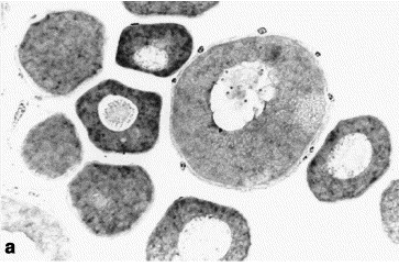

Image published in: Vaccaro MC (2003)

Copyright © 2003. Image reproduced with permission of the Publisher, Elsevier B. V.